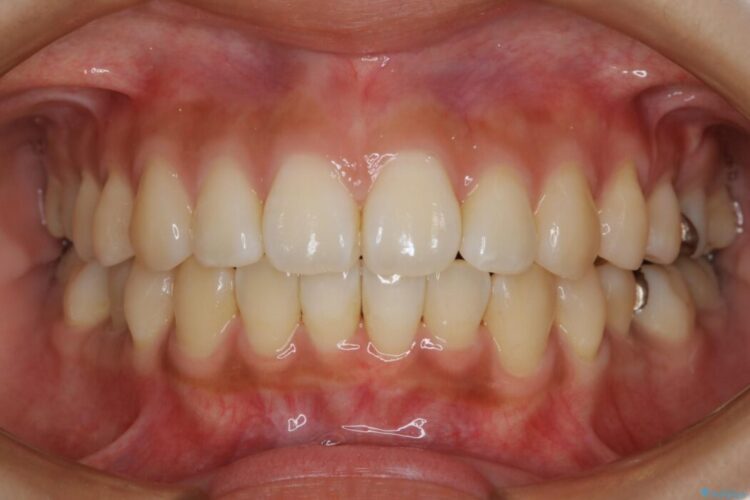

【20代女性】非抜歯でマウスピースの限界に挑戦する矯正治療

治療後について

患者様の意識も高く、しっかりとマウスピースを装着していただけたこともあり満足できる仕上がりとなりました。

本症例では最大量の移動もあり治療期間が掛かってしまいましたが、非抜歯でマウスピース矯正をしたいというご希望に応えることができました。